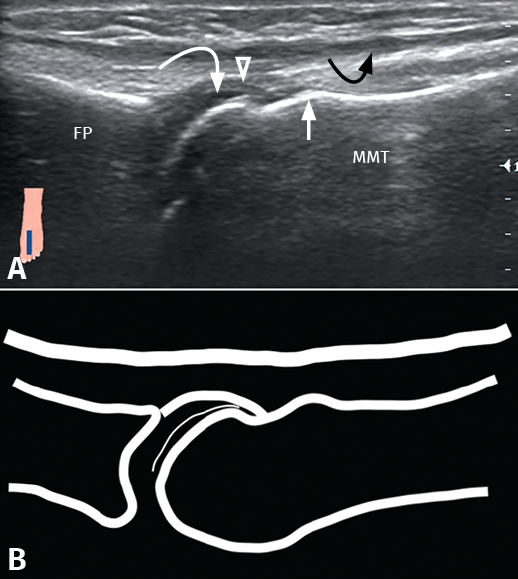

Figura 1. Estudio ecográfico en plano longitudinal. A: imagen ecográfica; B: representación esquemática. FP: falange proximal; MTT: metatarsiano; flecha blanca: giba dorsal; flecha blanca curva: cartílago articular; cabeza flecha blanca: cápsula articular; flecha negra curva: tendón extensor.

Las variables sobre las que se analizó la concordancia ecográfica son las estructuras anatómicas del campo quirúrgico. Entre ellas, definimos estructuras propiamente óseas como: a) la articulación MTF; b) la base de la falange proximal; y c) la giba dorsal, un relieve característico en el dorso de la metáfisis metatarsal, también visible mediante radiología convencional y que se encuentra inmediatamente proximal a la inserción capsular en el cuello metatarsal. Entre las estructuras no óseas, definimos: a) los tendones extensores; b) la cápsula articular dorsal; c) el cartílago articular de la cabeza metatarsal; y d) el paquete vasculonervioso. Incluimos, asimismo, una medida arbitraria: la distancia entre la interlínea articular y el área dorsal desnuda, o punto de inserción de la cápsula articular en el dorso del cuello metatarsal.

Para la identificación de las variables se utilizó un ecógrafo M-Turbo® Ultrasound System, con un transductor plano lineal HFL50x® (Sonosite, Fujifilm, Tokio, Japón), con un rango de frecuencia de 6-15 MHz. Con el paciente en decúbito supino, se colocó el tobillo en flexión plantar y la articulación MTF en posición de flexoextensión media. Se inició el estudio en el plano longitudinal, con el transductor paralelo al eje metatarsiano y se registró la visualización o la ausencia de visualización de cada una de las variables previamente descritas (Figuras 1 y 2), excepto la identificación del paquete vasculonervioso, que fue llevada a cabo mediante ecografía Doppler en el plano transversal. Cada una de las imágenes en las que el cirujano es capaz de identificar las estructuras se guardaron en un archivo de imágenes que posteriormente fue analizada por el radiólogo para establecer la variabilidad interobservador. La medición de la distancia interlínea articular-área dorsal desnuda y la identificación del paquete vasculonervioso fueron llevadas a cabo por el propio radiólogo en cada uno de los voluntarios sin basarse en las imágenes estáticas tomadas por el cirujano. El cirujano repitió la misma exploración ecográfica en cada uno de los voluntarios en días no consecutivos para analizar la concordancia intraobservador.